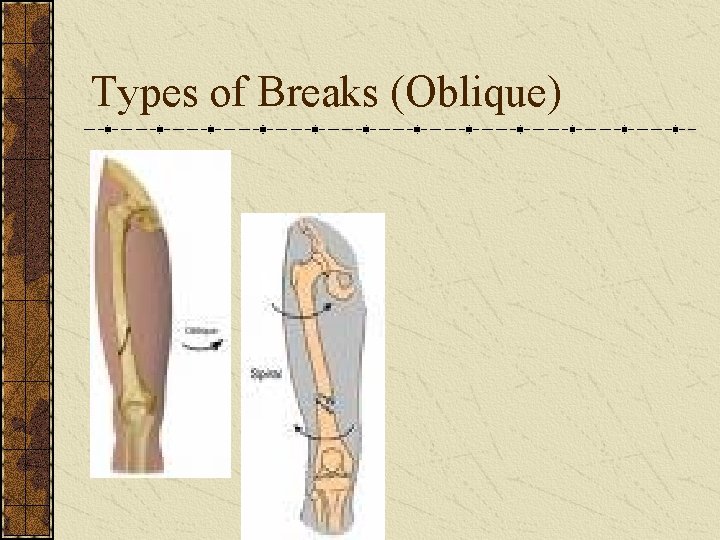

Types of Breaks There are five different types of fracture: 1. Transverse: Straight across bone 2. Oblique: Diagonal break across bone 3. Spiral: Around the bone 4. Comminuted: Bone is shattered 5. Greenstick: Bone breaks like a stick

Types of Breaks (Oblique)

Types of Breaks (Spiral)